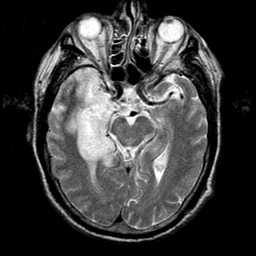

Herpes Encephalitis: T2-weighted MR -- Slice #12

In this set of images, there is a region of very bright signal on MR (and high blood flow on SPECT; use the buttons at right) in the medial temporal lobe at left (patient's right). This corresponds to an area of active viral leptomeningeal and brain tissue infection. Hemorrhage can occur acutely, but is not seen in this case. You can see obliteration of the temporal horn of the lateral ventricle because of swelling of the hippocampus. The remainder of the brain is relatively hypoperfused (use the buttons at right) and structurally normal. The MR images were obtained 5 days after onset of symptoms, and the follow-up SPECT 23 days later.